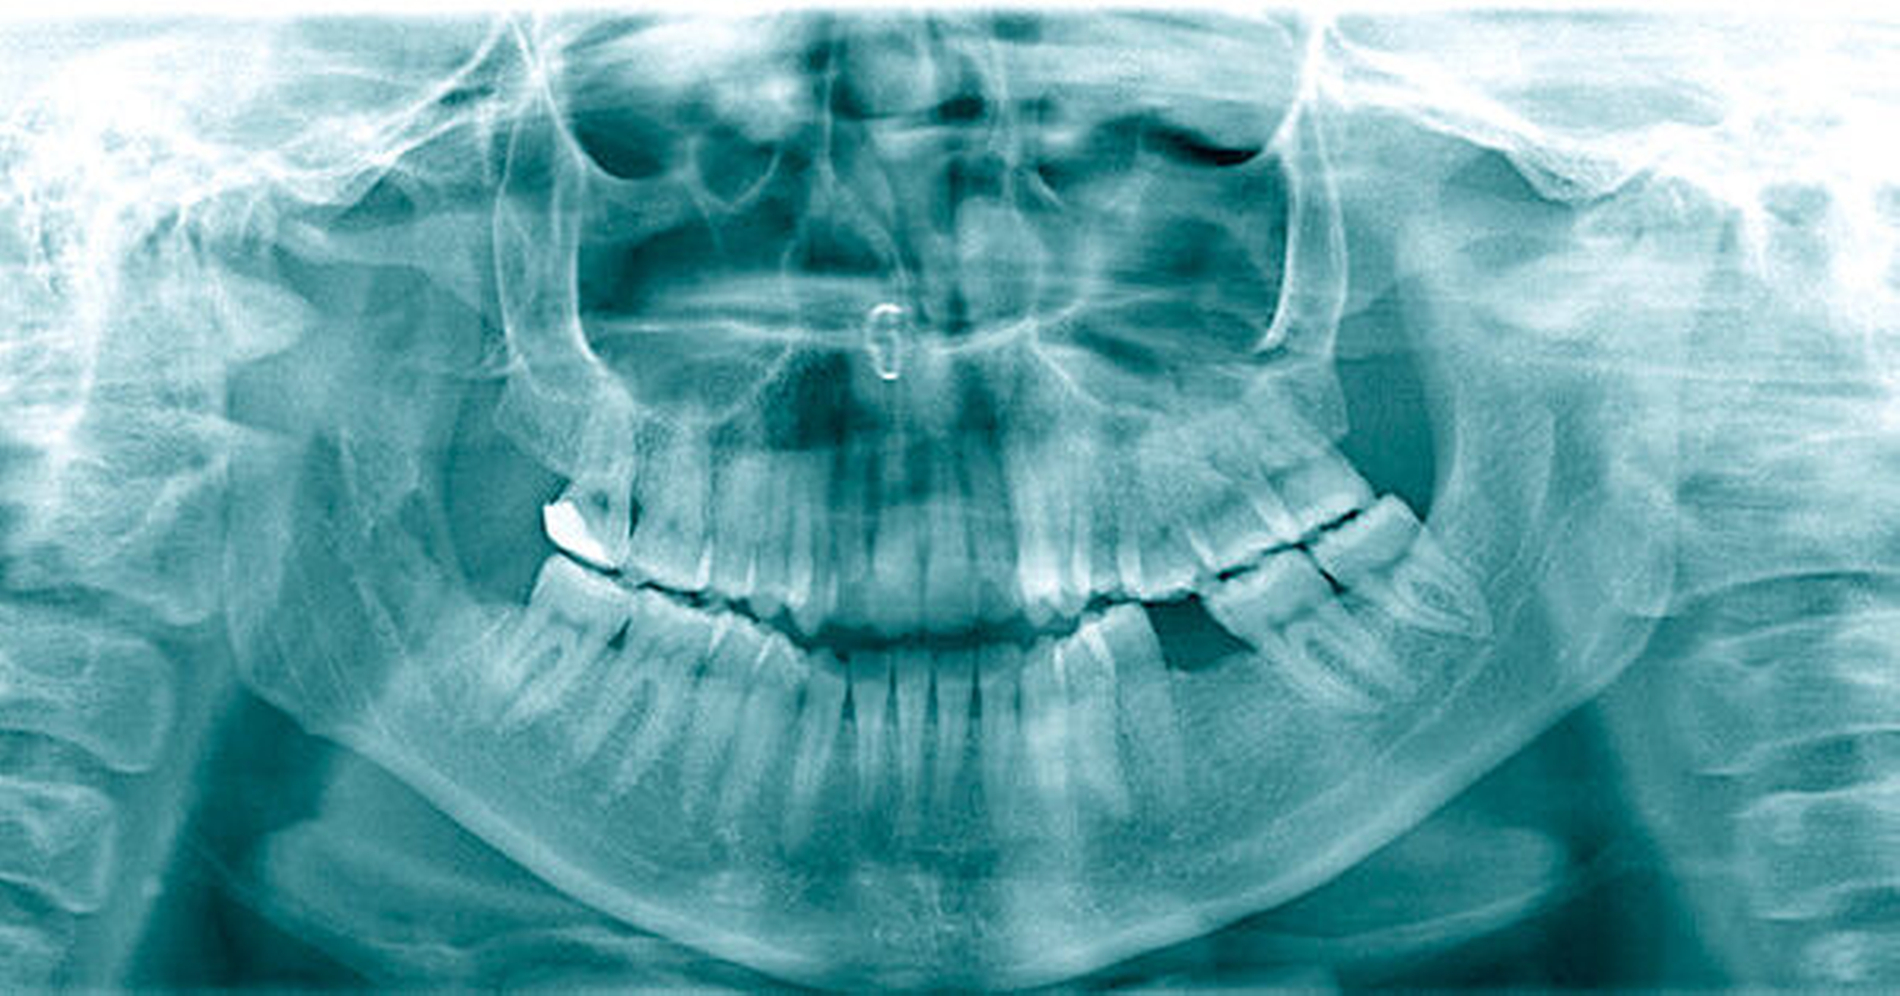

Abbildung 1 dokumentiert den Röntgenbefund des ersten und des vierten Quadranten. Bei Verdacht auf eine Neurotmesis des rechten N. lingualis (lingual nerve; LN) und eine Axonotmesis des rechten N. alveolaris inferior (inferior alveolar nerve; IAN) während der Weisheitszahnentfernung wurde nach Erörterung der Therapiemöglichkeiten mit der Patientin die Indikation zur zeitnahen operativen Nervendarstellung und -rekonstruktion gestellt.

Postoperativ berichtete die Patientin über eine Verbesserung der Sensibilität im Bereich des Unterkiefers rechts sowie über ein gelegentliches Kribbelgefühl im Bereich der Zunge rechts. Zur Verbesserung der körperlichen Nervenregeneration wurde Vitamin B12 oral substituiert. Abbildung 5 dokumentiert die postoperative Röntgenkontrolle.